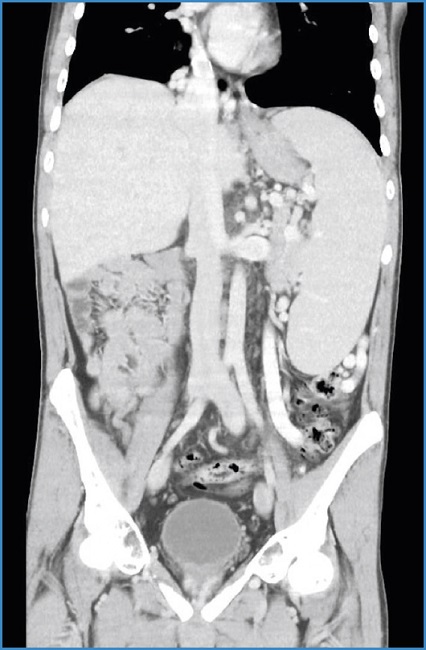

En el posoperatorio inmediato, el paciente desarrolló cuadro compatible con shock hemorrágico, por lo que fue trasladado a la unidad de cuidados intensivos. Se inició tratamiento vasopresor y politrasfusión y se consiguió estabilizar al paciente. Se realizó angio-TAC abdominal, en el que se objetivó hematoma retroperitoneal de predominio derecho de 4 × 7 cm (diámetros anteroposterior AP y transversal T), así como imagen sugestiva de pseudoaneurisma de la VCI distal (36,7 mm AP × 36,9 mm T), con afectación de bifurcación ilíaca y sin signos de hemorragia activa (Fig. 1). Ante este hallazgo se avisó al Servicio de Cirugía Vascular.

Figura 1. Angio-TAC inicial. Lesión dependiente de VCI sin signos de hemorragia activa (flecha verde) y con hematoma retroperitonal extenso.